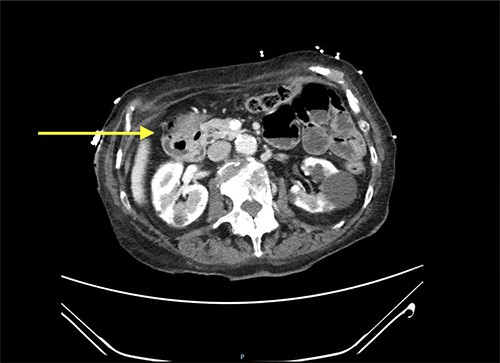

Abdominal CT scan showed a small intussusception involving the pylorus of the stomach and the first part of the duodenum with approximately 18-mm segment of the pylorus telescoping into the first part of the duodenum. This, however, did not cause a significant obstruction to the gastric outlet and the stomach was collapsed. No lead point mass or lesion identified within the limitations of the study.

The rest of the duodenum and small bowel loops are unremarkable (Figs 1 and 2).